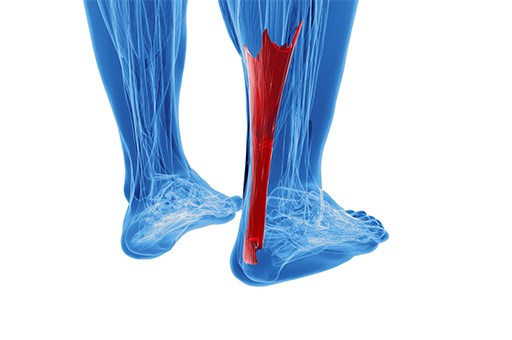

Pain in the foot and ankle joint is a fairly common problem that occurs in patients, especially those who are physically active. Ankle pain can be related to pain in the bone itself, pain in the tissues around the bone, such as the tendons of the fibular muscles, or it can be pain related to ligament damage, such as after an ankle sprain.